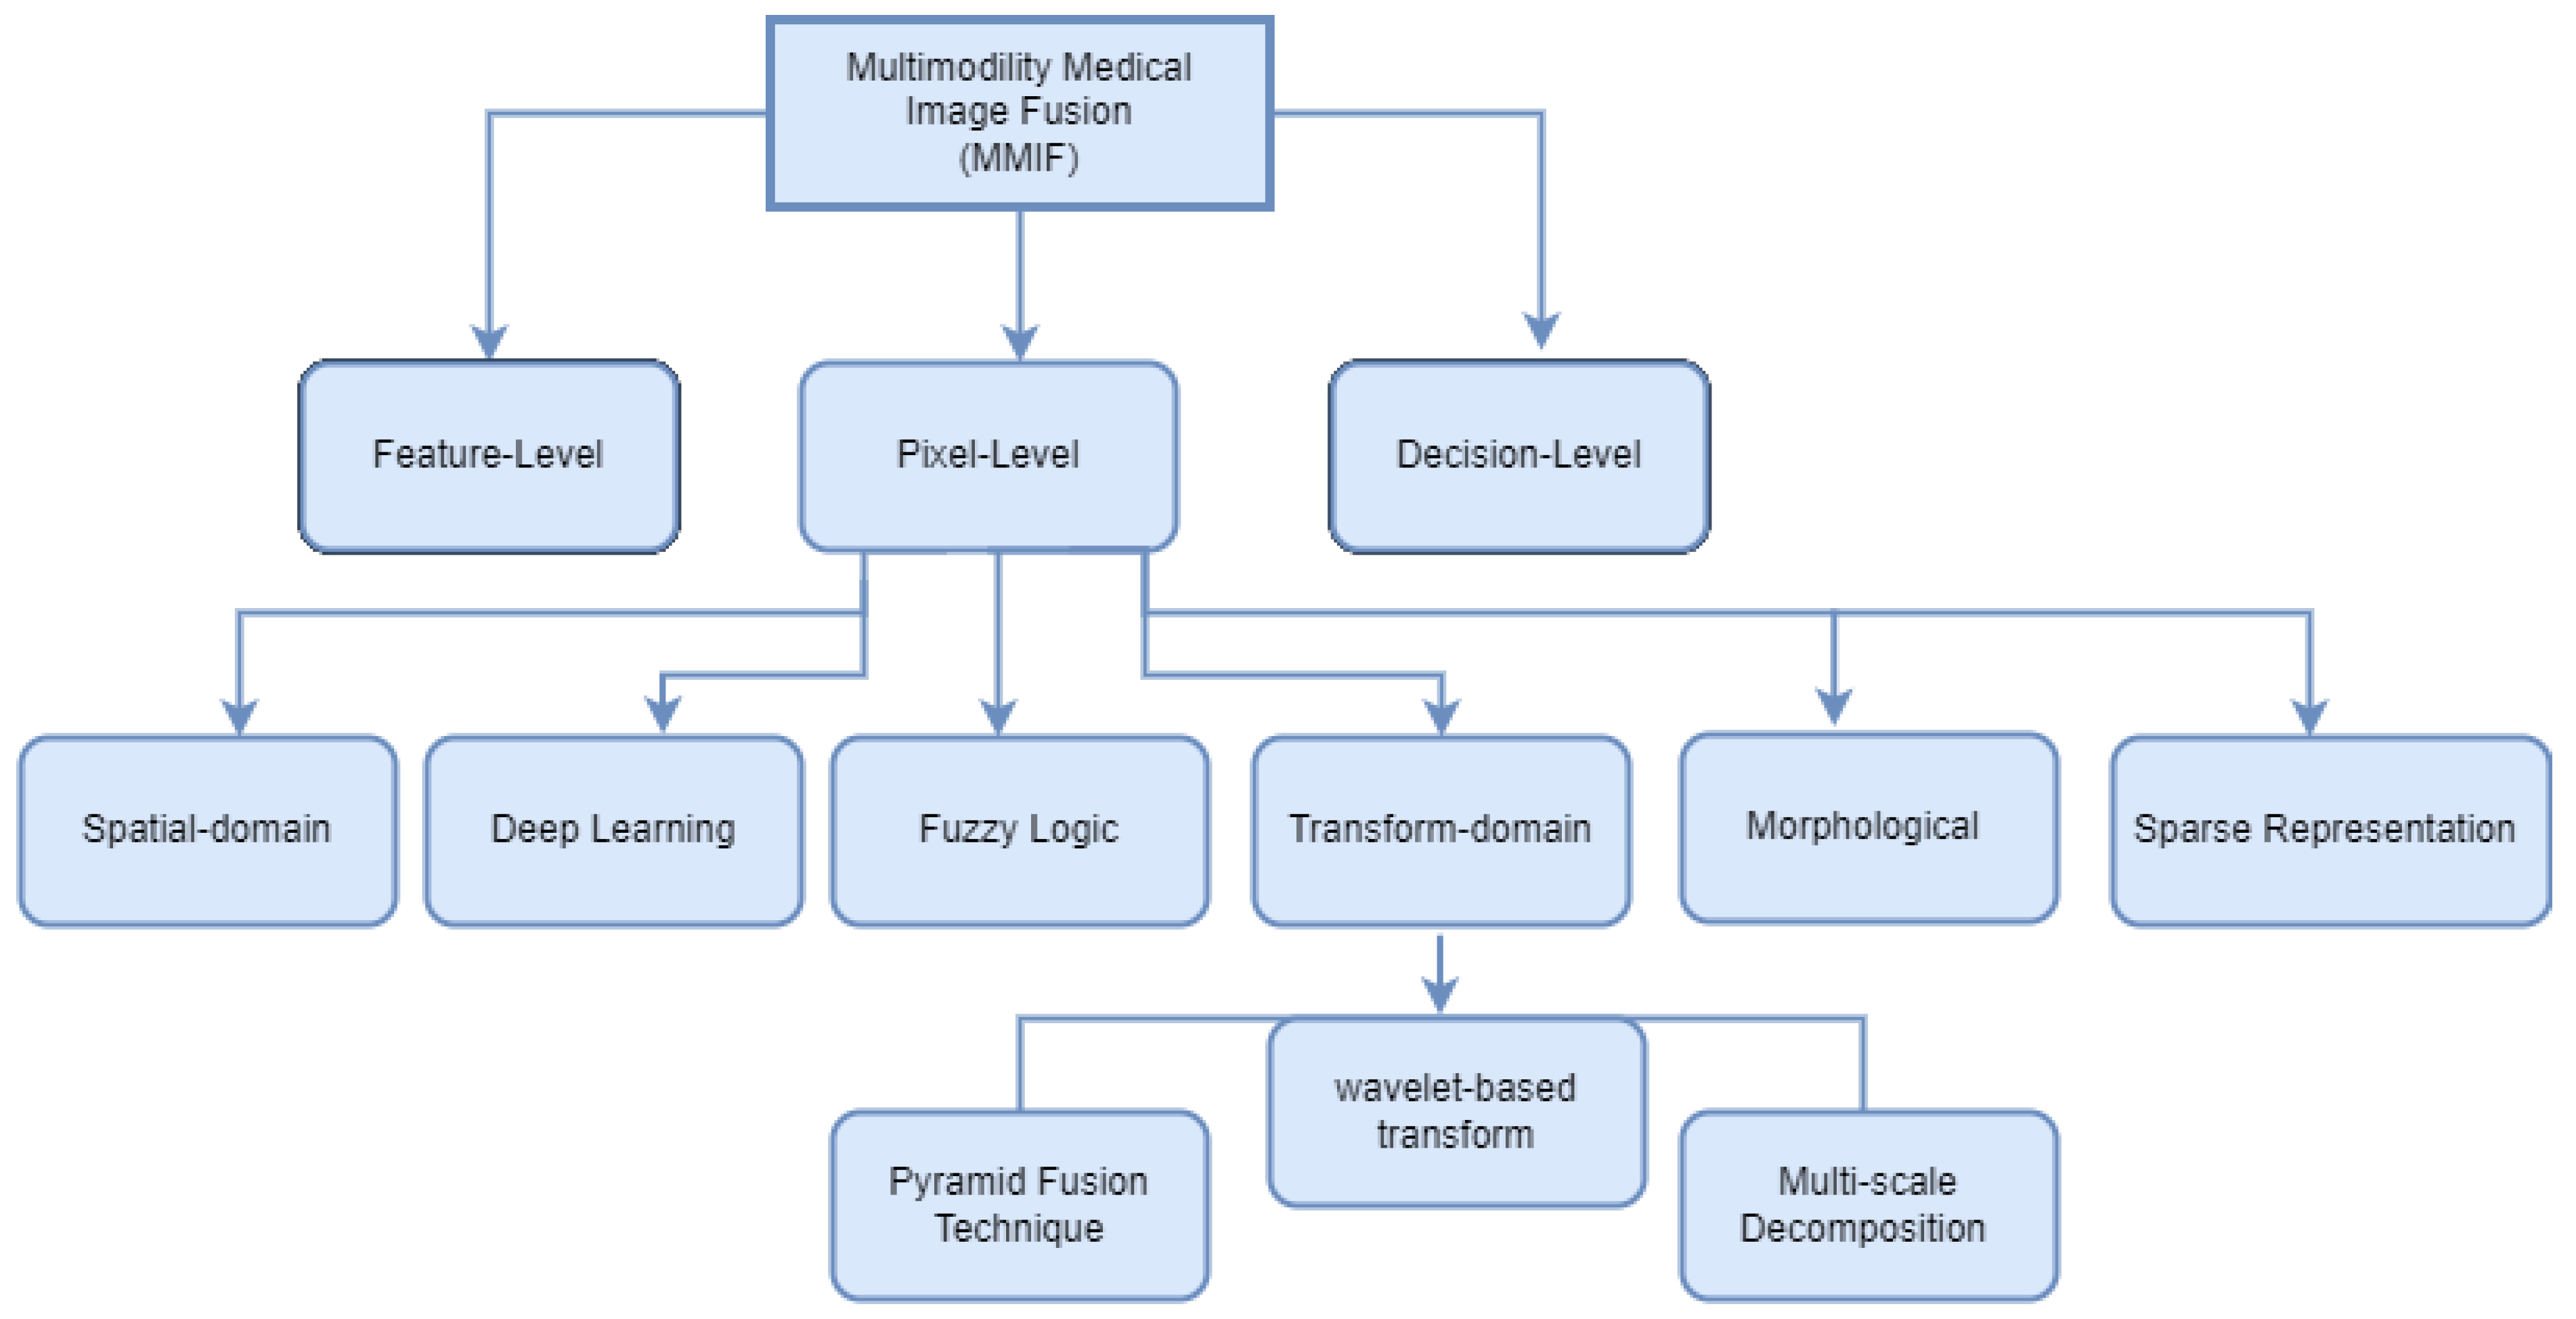

4. MMIF Levels

4.1. Pixel-Level Fusion

4.2. Feature-Level Fusion

4.3. Decision-Level Fusion (Dictionary)

5. Image Fusion Techniques